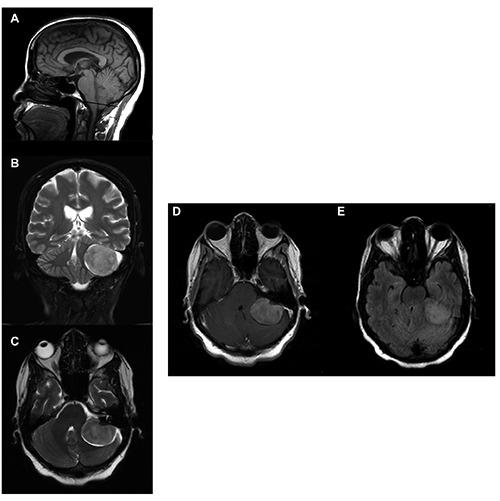

A 56-year-old Afro-Trinidadian woman with a history of a carbidopa-levodopa resistance Parkinsonian-like syndrome for 2 years, presented with acute onset spastic quadriplegia and decreased responsiveness. Diagnosis involved clinical and MR-imaging correlation consistent with a large left posterior fossa meningioma. Surgical removal of the tumor led to complete reversibility of the neurological manifestations associated with cerebellar tonsillar herniation beyond the foramen magnum and mass effect on the brainstem, cerebellum and midbrain regions. Pathological findings were typical of a meningioma. This case demonstrates the association of a large left posterior fossa meningioma and carbidopalevodopa resistant parkinsonism in an Afro-Trinidadian woman who presented with acute onset acute quadriplegia and decreased responsiveness. This case reminds clinicians that patients with dopa unresponsiveness and/or acute neurological deficit or deterioration should be worked up for other possible causes and adds to the literature on the association of parkinsonism and intracranial space occupying lesions.

一名56岁的非裔特立尼达妇女,患有对卡比多巴-左旋多巴耐药的帕金森样综合征2年,出现急性起病的痉挛性四肢瘫和反应迟钝。诊断通过临床与磁共振成像相关性得出,符合左侧后颅窝大型脑膜瘤。手术切除肿瘤后,与小脑扁桃体疝出枕大孔及对脑干、小脑和中脑区域的占位效应相关的神经学表现完全可逆。病理结果为典型的脑膜瘤。该病例显示了一名非裔特立尼达妇女左侧后颅窝大型脑膜瘤与卡比多巴-左旋多巴耐药帕金森病的关联,该妇女表现为急性起病的急性四肢瘫和反应迟钝。该病例提醒临床医生,对多巴无反应和/或有急性神经功能缺损或恶化的患者应排查其他可能病因,并为帕金森病与颅内占位性病变的关联文献增添了内容。